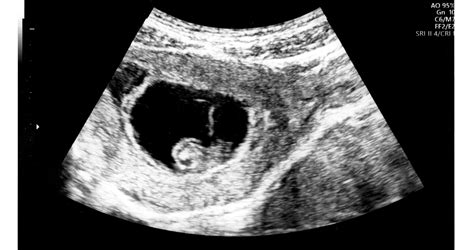

A méhlepények számát az első trimeszteres ultrahang vizsgálat során állapítják meg. Ha egypetéjű ikreknél csak egy méhlepényt találnak, akkor számíts még több vizsgálatra és még alaposabb monitorozásra az egész várandósság alatt! Egy méhlepény esetén valószínűleg beutalnak kardiológiai ultrahang vizsgálatra is és a utolsó hetekben már jó eséllyel a kórház vendégszeretetét fogod élvezni, azért, hogy naponta tudják vizsgálni a babákat és kizárni az iker-iker transzfúzió veszélyét.